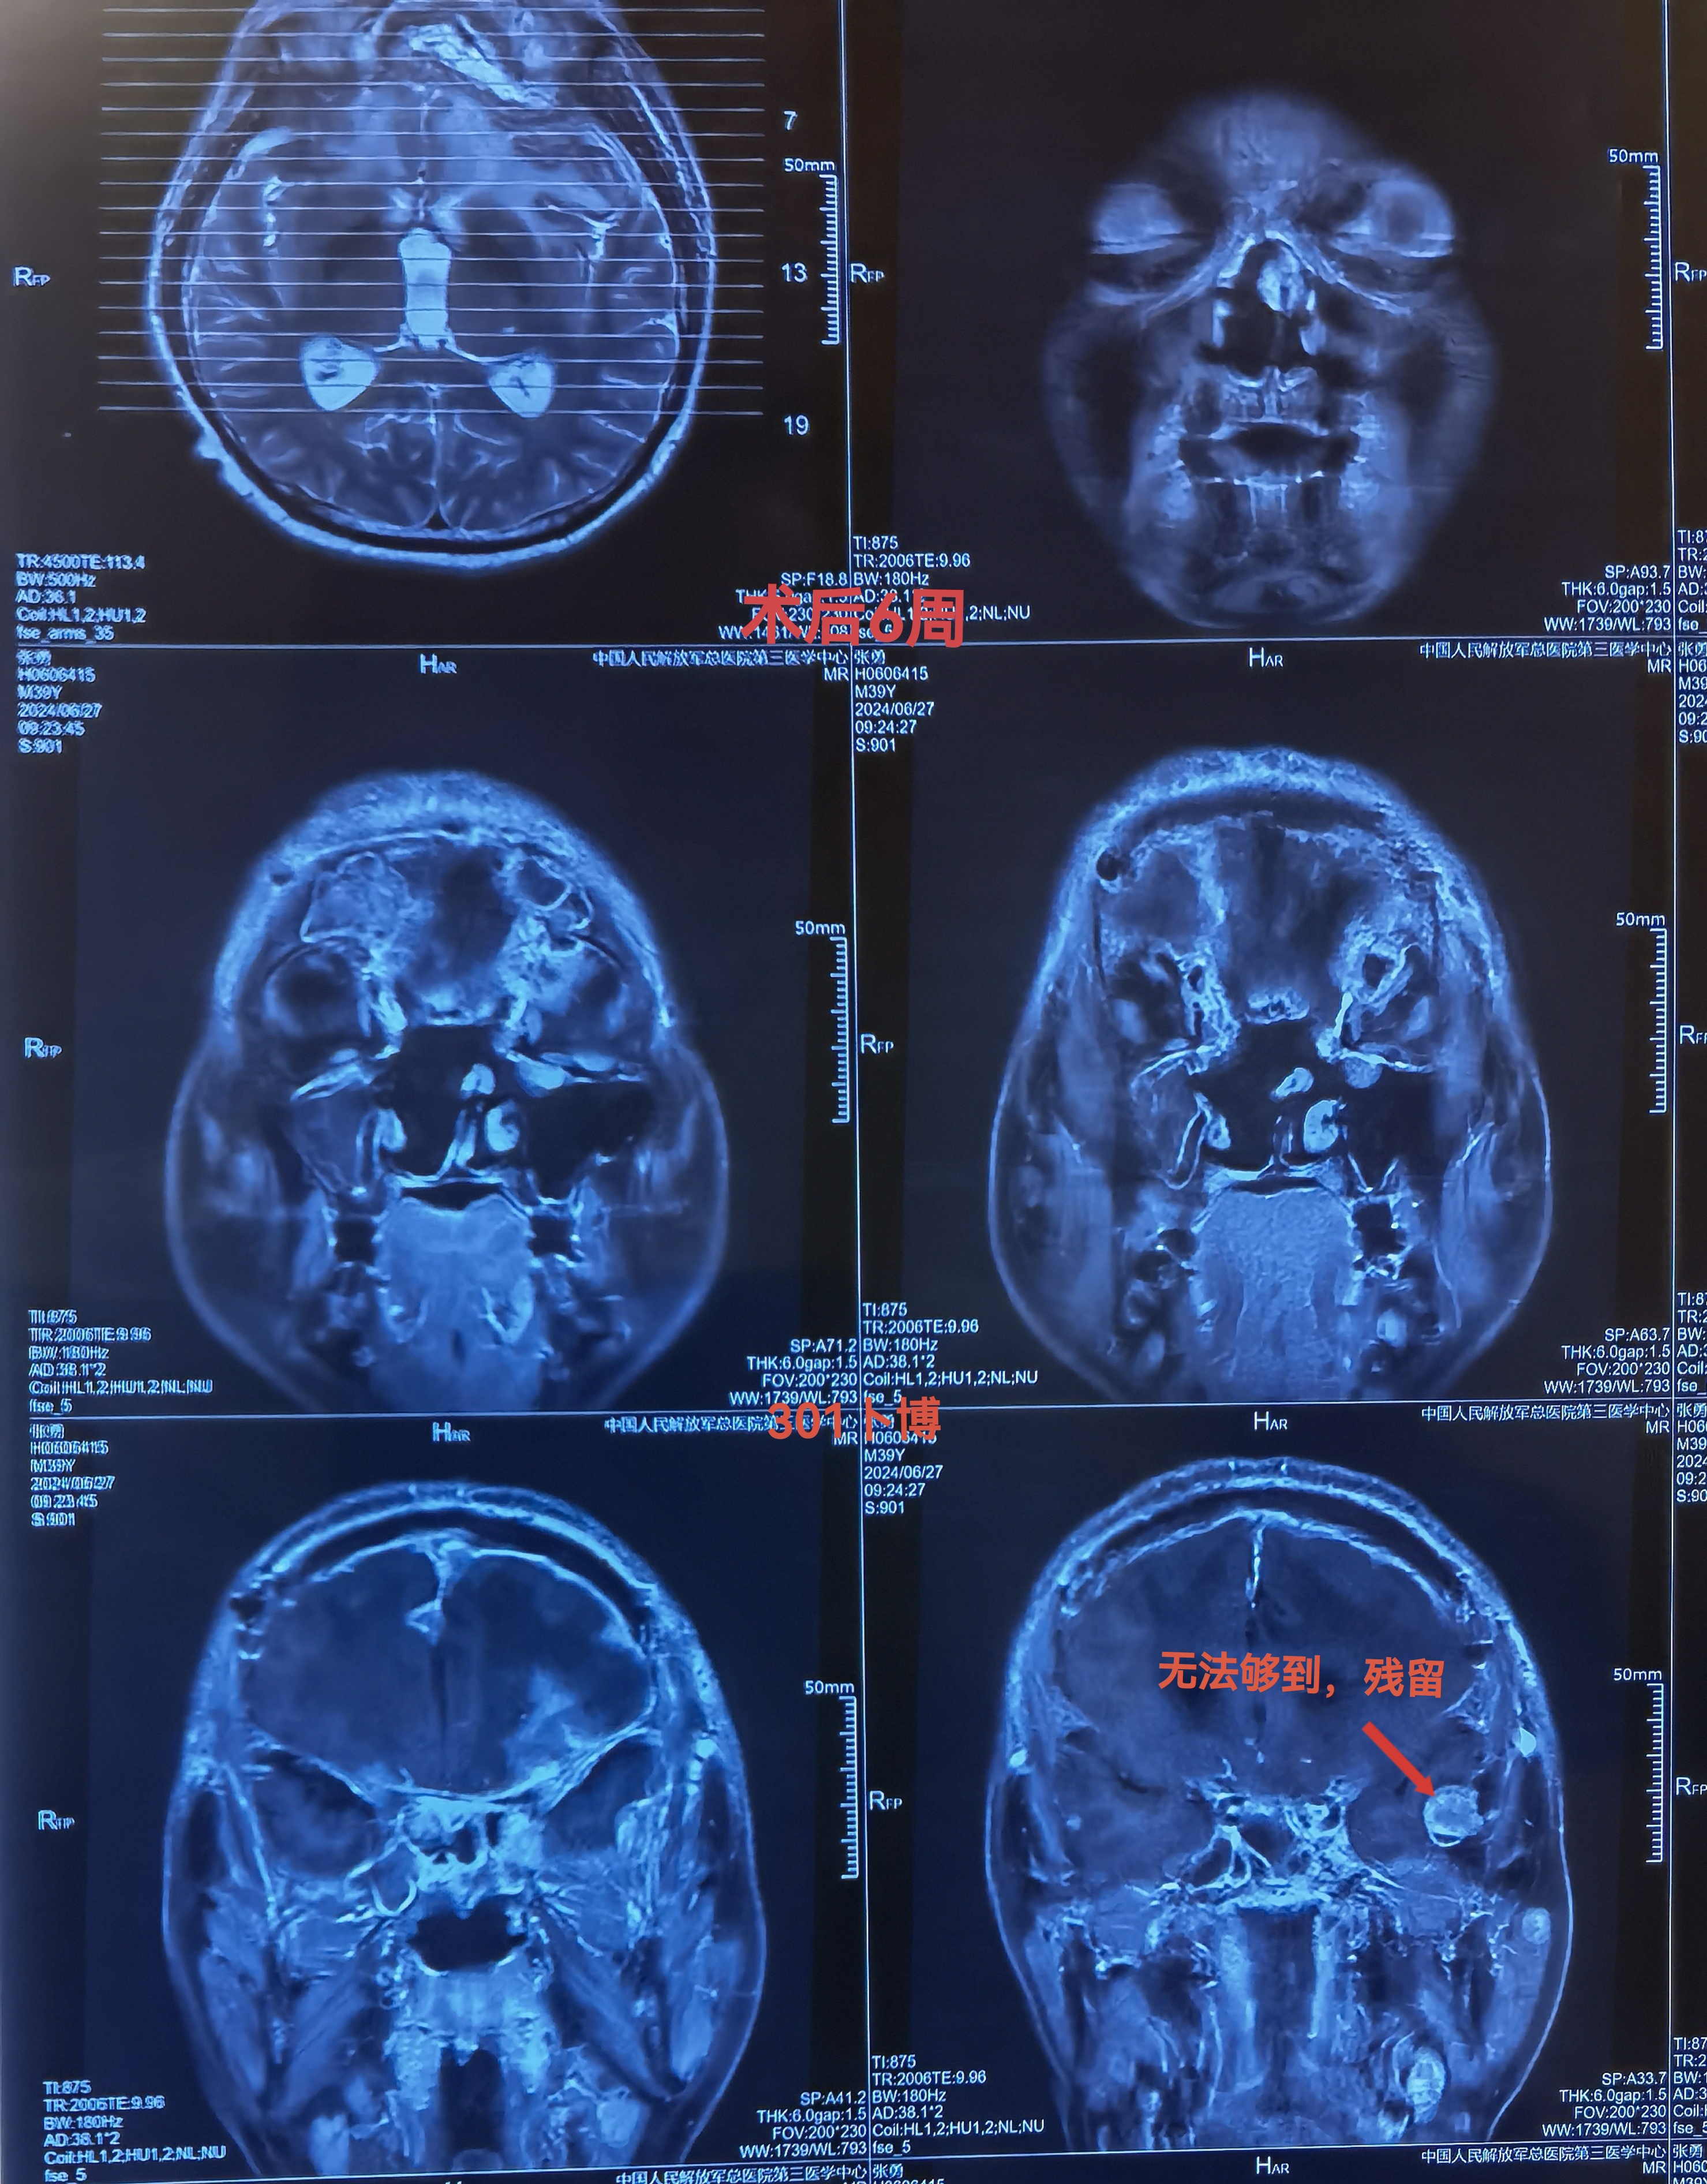

CT扫描可见颅内等密度占位,局部水肿明显,中线向右偏移。冠状位重建可见嗅沟蝶骨平台处骨质破坏导致缺损。

MRI可见肿瘤巨大,中鼻道以上,蝶窦筛窦及双侧额底均为肿瘤组织占据,向两侧到蝶骨嵴。肿瘤分叶状,可明显增强,核心区有坏死。后部可见粗大的静脉。双侧大脑前动脉位于肿瘤的后部。

肿瘤侵及颅鼻眶

肿瘤向后到鞍结节前床突,向外到两侧的蝶骨嵴。

CT与增强MRI的对比